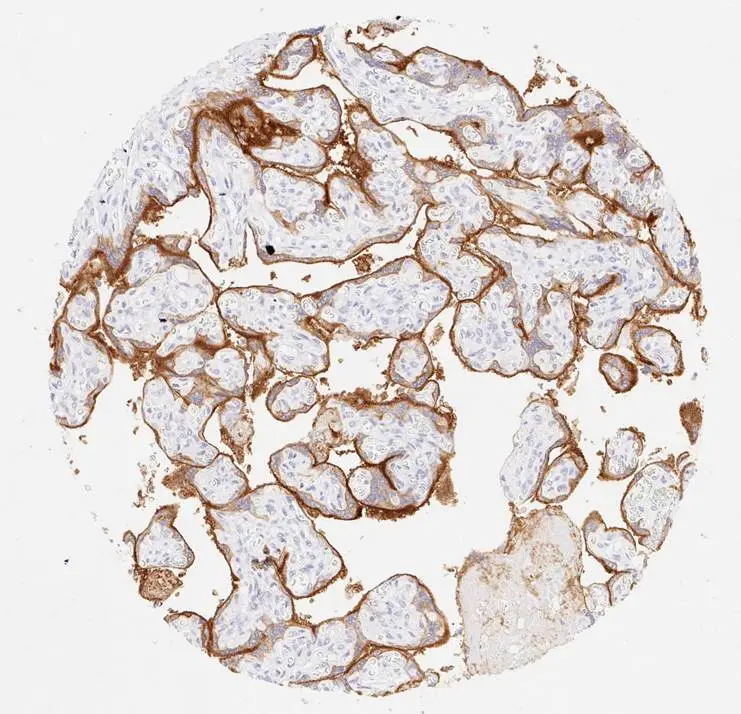

IHC-P analysis of human oropharyngeal squamous cell carcinoma (OPSCC) tissue using GTX639925 PD-L1 antibody [H302] HistoMAX™.

Strong membranous PD-L1 positivity of the stroma-adjacent (peripheric) tumor cell layers of a squamous cell carcinoma of the pharynx.